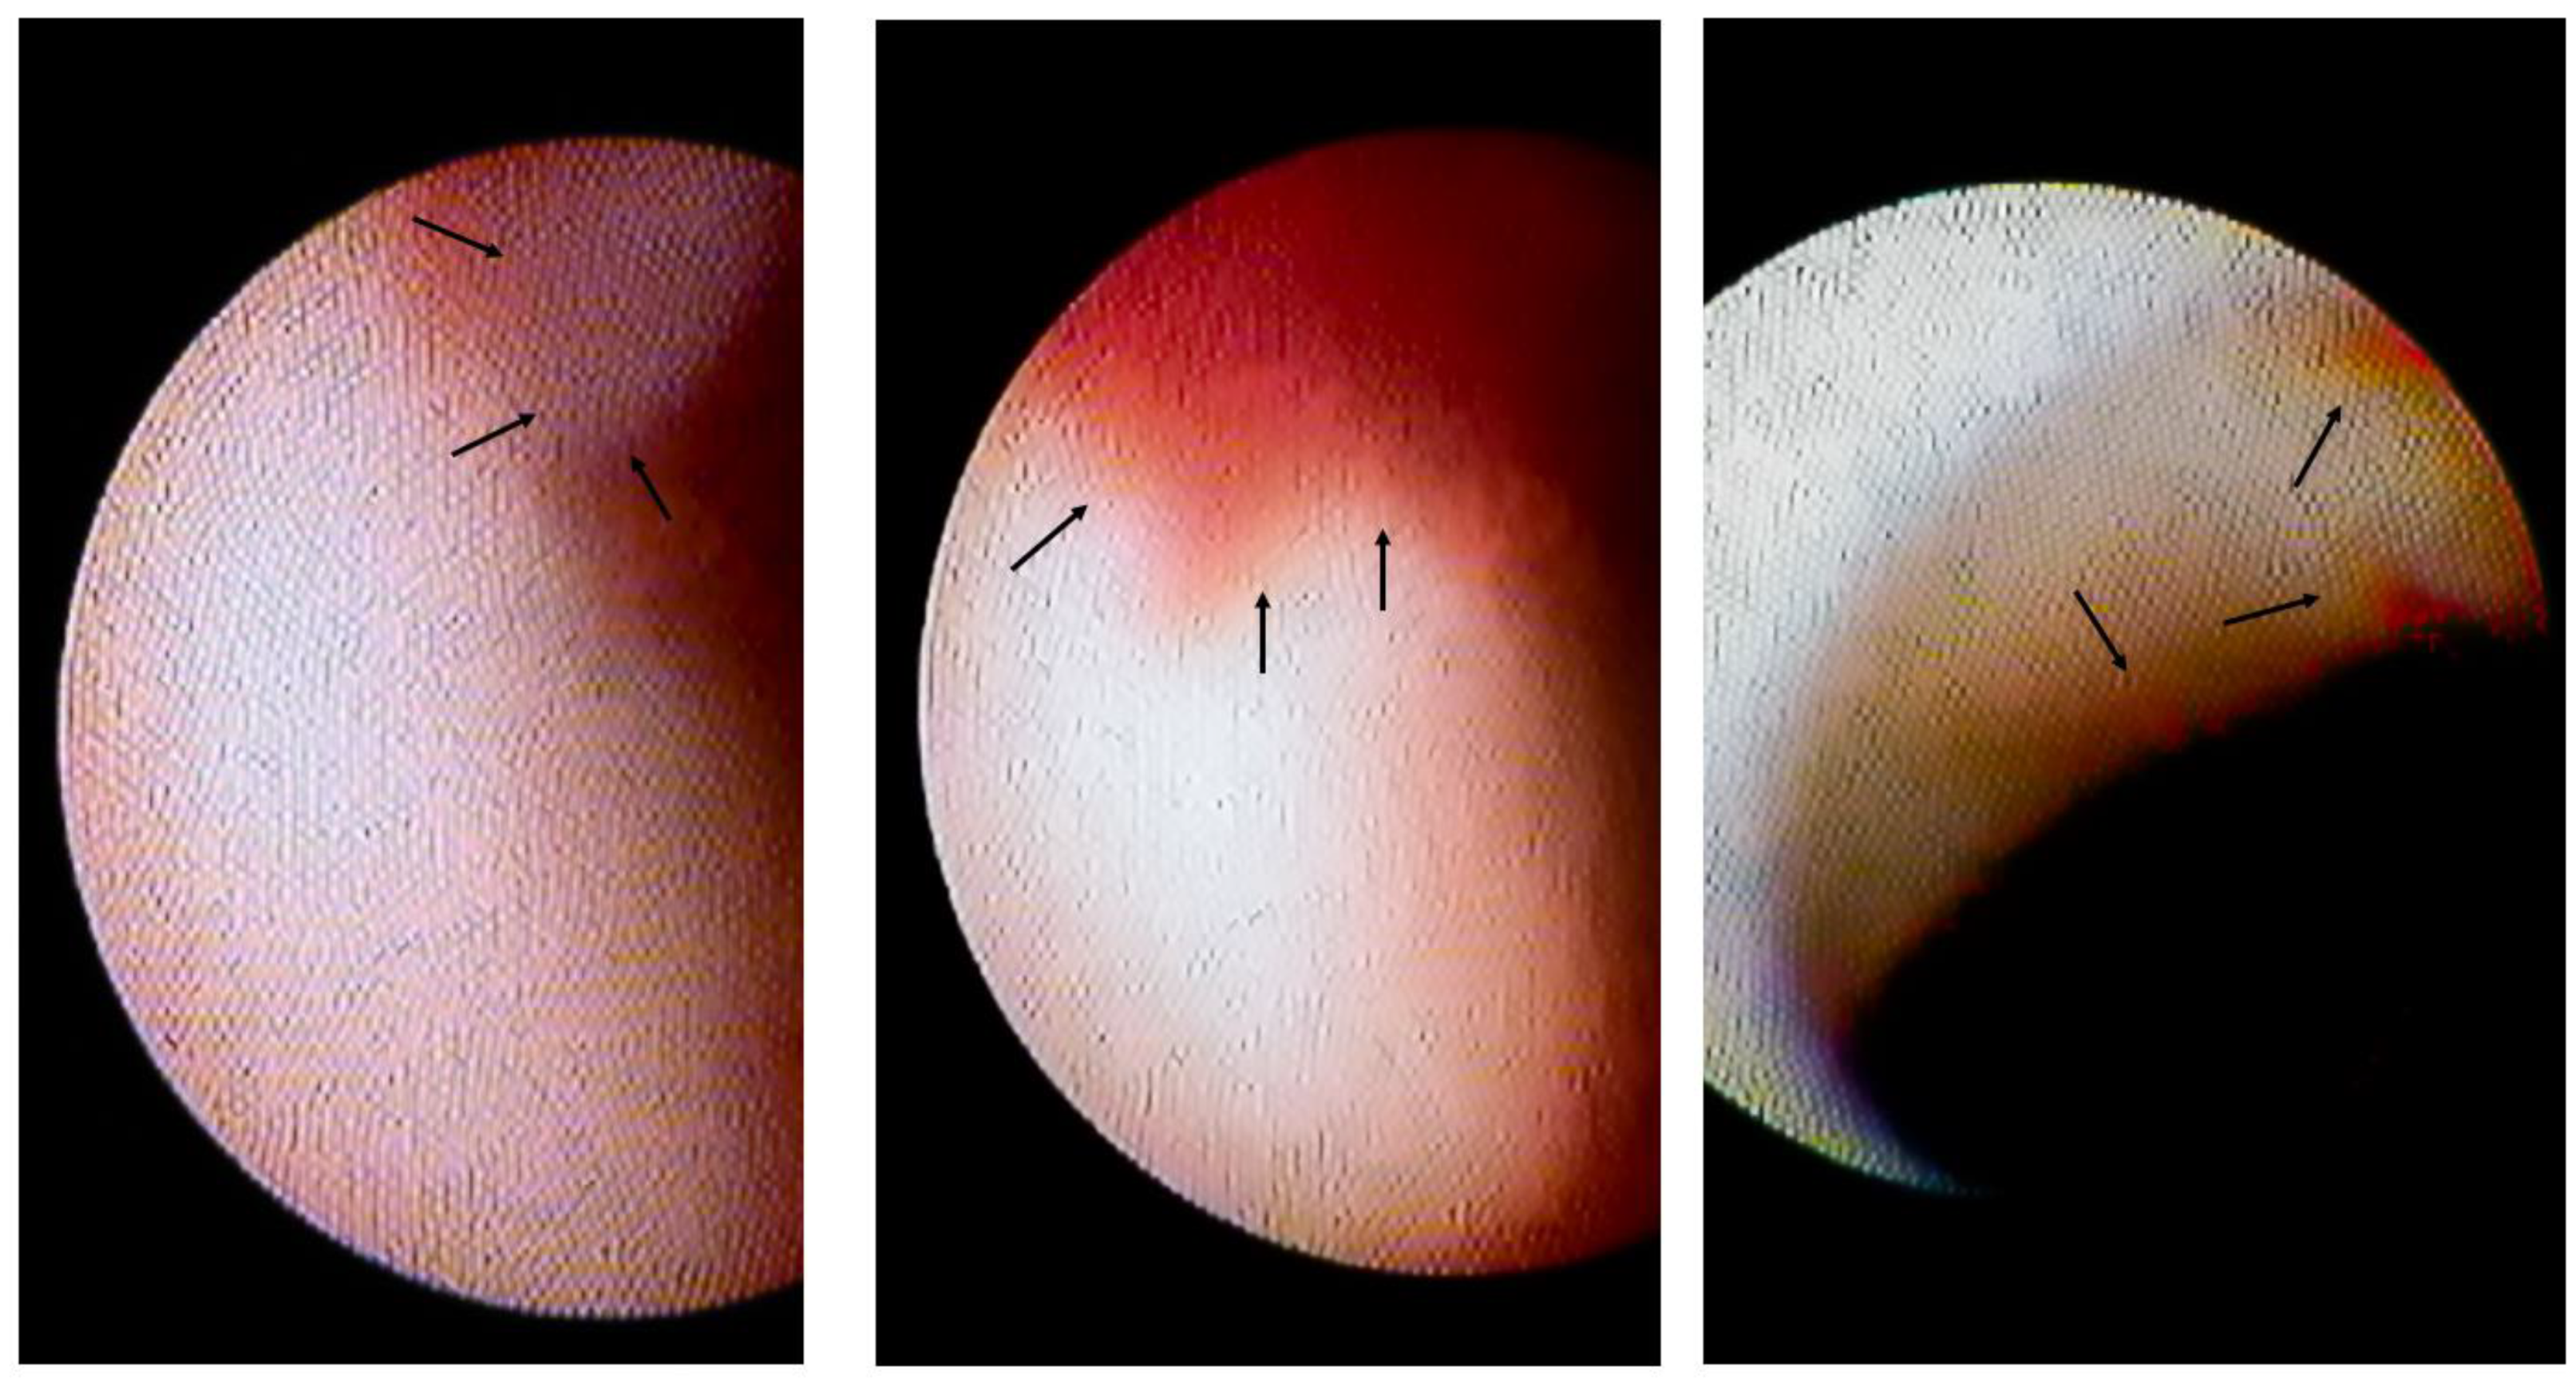

3.2. Lesion Characteristics with Intracoronary Thrombi